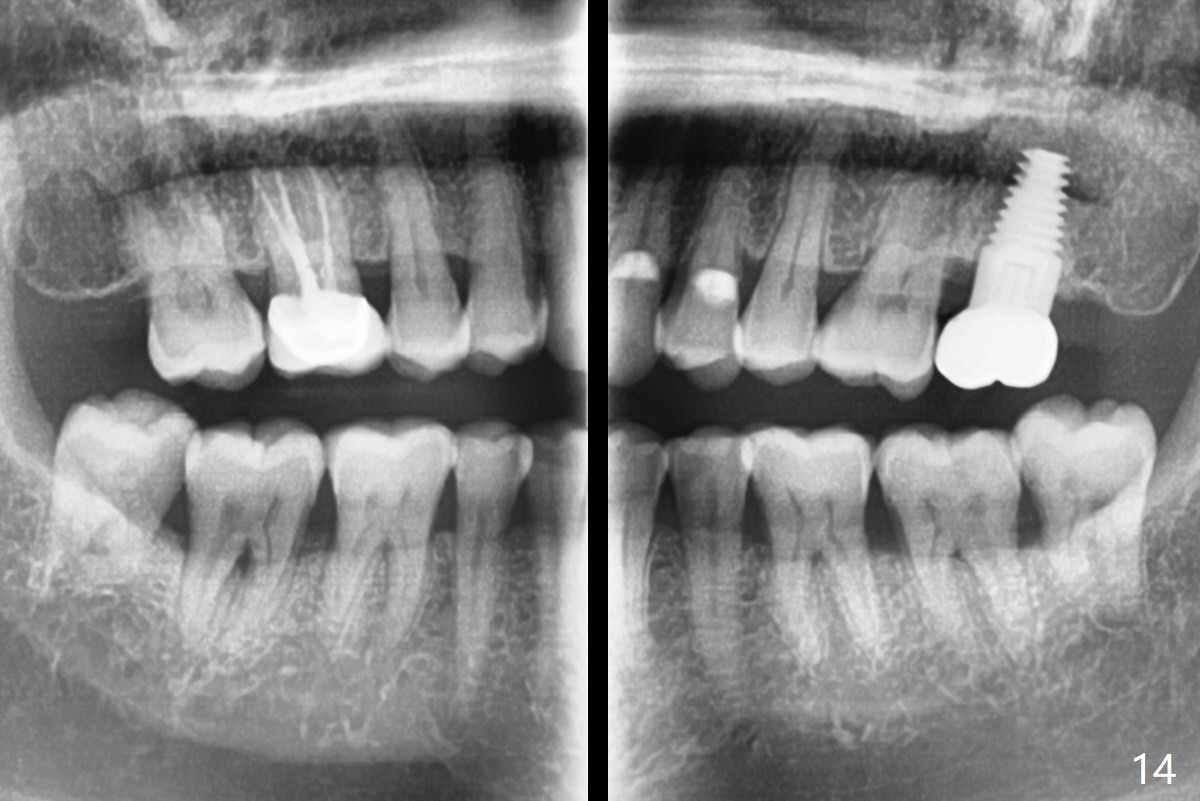

A 50-year-old man (TK) had sign & symptom of crack tooth at #15 (Fig.1) and chose to have root canal therapy done by a specialist. One month later, he returns for crown; exam reveals a crack line mesiodistally (Fig.2). The patient agrees to have immediate implant (Fig.3 design: 6x14 mm). The buccal roots fracture upon luxation. Osteotomy starts in the septum with a 2 mm pilot drill and deviates to the palatal socket, followed by 2, 3, 4 mm tapered osteotomes. A series of taps are placed: 6x17 mm one achieves stability (Fig.4). When the latter is removed, there is no sign of sinus air leakage. A 6x14 mm implant (Fig.5 I) and a 5x3 mm abutment (A) are placed. After abutment height adjustment, an immediate provisional is fabricated. Allograft with Osteogen is placed in the remaining sockets and gaps (Fig.6 *). Fig.7 shows the inner side of the provisional with double arrows indicating the dimension of the abutment, whereas arrowheads the dimension of the socket buccopalatally. When the provisional is cemented (Fig.8 P), it completely seals the socket. As long as the provisional stays, bone graft will not be lost.

There is no bone loss 17 months post cementation (Fig.12). The patient reports that he has to keep cleaning well to prevent discomfort locally. Clinically, the gingiva is healthy around the implant crown. No bone loss is around the implant 3 years 8 months post cementation (Fig.13), but the natural teeth are not so fortunate (Fig.14).